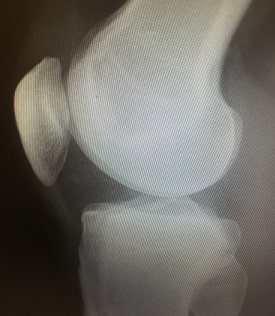

ひざの痛みがある時、考えられる病気を診断するために、問診、視診、触診、画像検査(X線撮影、CT、MRI)、関節液検査、血液検査、リウマチ因子検査、関節鏡検査、関節造影検査などを行います。